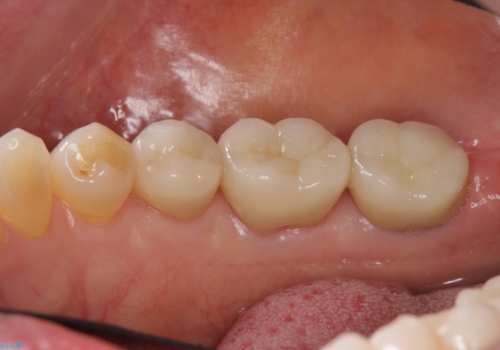

[ 歯冠長延長術 ] クラウンスペースの確保を行い抜歯を回避

![[ 歯冠長延長術 ] クラウンスペースの確保を行い抜歯を回避の症例 治療前](https://seimitsushinbi.jp/wp/wp-content/uploads/2024/08/70e2e357470ac1fd6c1489f5d90a7b82-500x350.jpg?v=1724393985)

![[ 歯冠長延長術 ] クラウンスペースの確保を行い抜歯を回避の症例 治療後](https://seimitsushinbi.jp/wp/wp-content/uploads/2024/08/55bc634e756d10cce362016c1293fafc-500x350.jpg?v=1724393990)